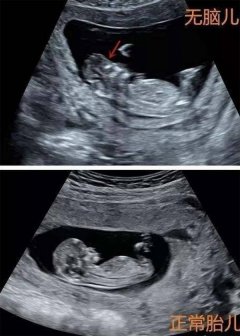

无脑儿 胎儿 叶酸 2024/11/27